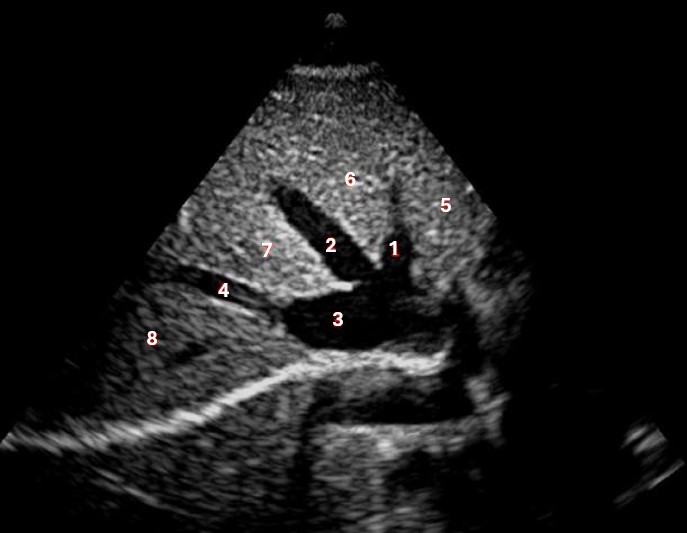

Which of the following structures is labeled #5?

lateral left lobe |

What lobe of the liver is indicated by #1?

posterior right lobe

What structure/vessel is indicated by #8?

medial left lobe |

What lobe of the liver is indicated by #2?

anterior right lobe |

Which of the following structures is labeled #7?

anterior right lobe |

Which of the following structures is labeled #6?

medial left lobe |

Which of the following structures is labeled #3?

IVC

Which of the following structures is labeled #8?

posterior right lobe |